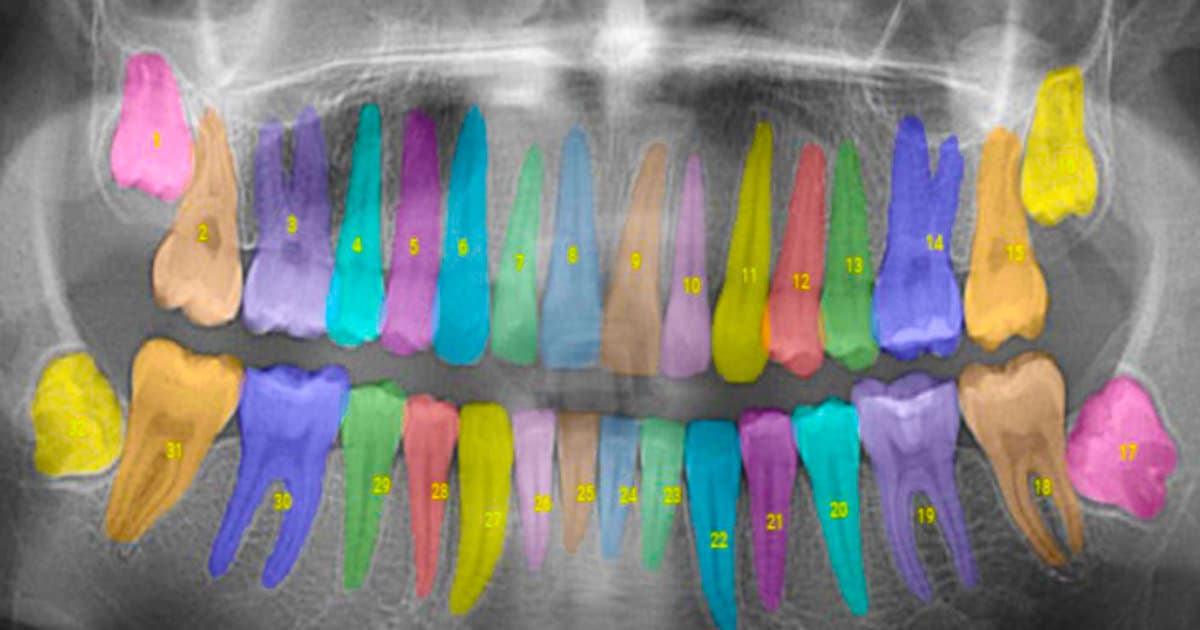

One of the most important things you can do for your oral health is to schedule regular check-ups with your dentist. These check-ups typically include a professional cleaning, where your teeth will be thoroughly cleaned and polished, and an examination, where your dentist will check for any signs of decay, infection or other problems. They can also take X-rays to check for any issues that may not be visible to the naked eye.